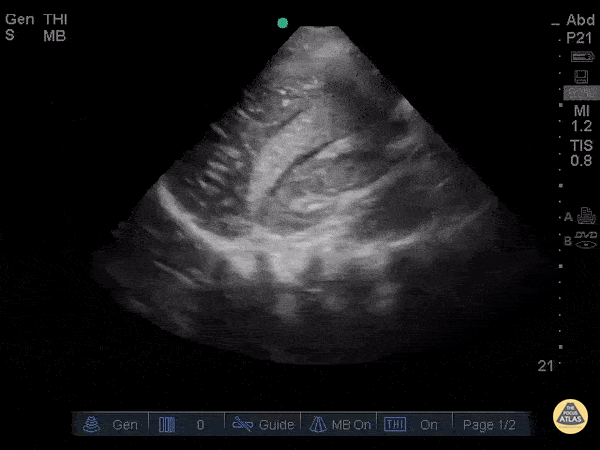

Trauma - Hemoperitoneum

This clip was obtained in a patient presenting after a fall from roof. This hepatic window demonstrates an echogenic clot surrounded by a thin sliver of anechoic free fluid. This patient had massive acute hemoperitoneum. Remember that not all acute hemorrhage is anechoic! Image courtesy of Robert Jones DO, FACEP @RJonesSonoEM Director, Emergency Ultrasound; MetroHealth Medical Center; Professor, Case Western Reserve Medical School, Cleveland, OH View his original post here